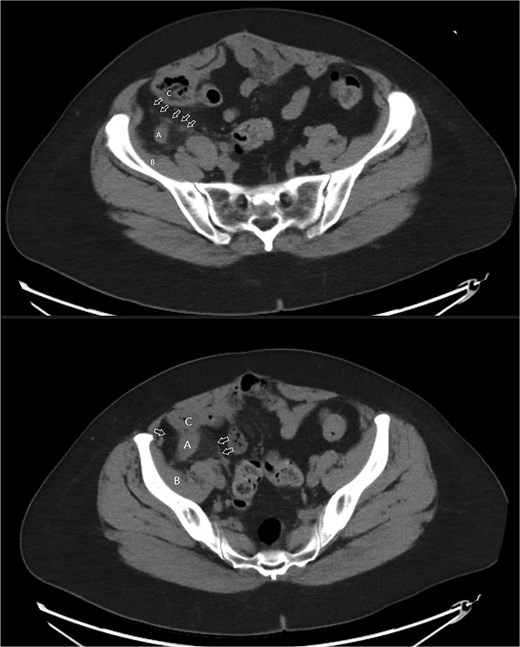

A 58-year-old female with a history of ovarian cancer, status post total abdominal hysterectomy, bilateral salpingo-oophorectomy, and omentectomy, presented with a 1-week history of right lower quadrant and right pelvic abdominal pain. Her labs were unremarkable. A CT scan of the abdomen and pelvis revealed a distended, fluid-filled appendix measuring 1.7 cm in diameter, with associated mesenteric infiltration and several small lymph nodes in the right lower quadrant, consistent with acute appendicitis (Fig. 1). The surgeon’s review of the scan was suspicious of retrocecal appendix (Fig. 2).

Axial images of CT scan with IV contrast showing appendix within retrocecal position in proximity within iliacus space. (A) Appendix; (B) iliacus muscle; (C) cecum.

Coronal image CT scan with IV contrast with arrows denoting appendix in proximity to iliacus space. (A) Appendix.